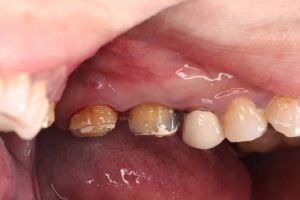

牙周翻瓣手術是最常見的牙周病手術療程,手術目的是清除牙齒和牙齦之間,更深層的細菌和壞死組織,減少牙周囊袋的深度,並促進牙齦再生,使牙齒更加穩固。

牙周囊袋是指牙齦與牙齒之間形成的空隙,裡面容易積累細菌和食物殘渣,導致牙齦發炎、出血、腫脹和萎縮,甚至造成牙齒鬆動或脫落。通常牙周囊袋的深度在5mm以上就已經是牙周病,7~8mm則為中度牙周問題,可能需要使用牙周翻瓣手術協助治療。

2 翻瓣:醫生會沿著牙齦邊緣劃開一條細長的口,將牙齦從牙齒上分離,露出牙根表面以利清理。

3 清理:醫生會用特殊工具清除牙根表面的細菌、組織和結石,消除感染源。